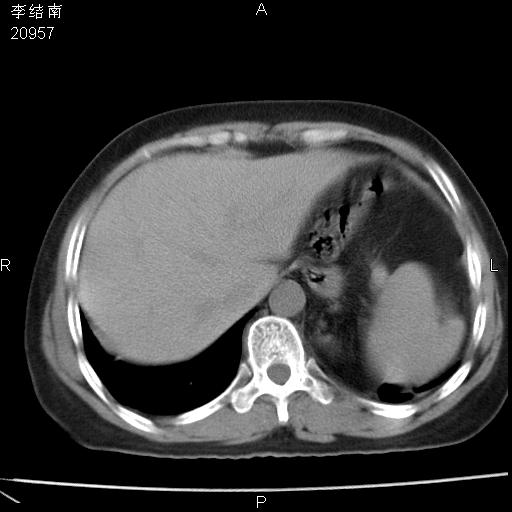

患者女,45岁,以右侧腰部包块来就诊,局部有压痛,皮肤颜色正常。因为是熟人扫的范围较大,患者有胆结石,胆源性胰腺炎病史。请大家看看,有手术病理。

可能大家觉得片子的质量不好,当时是做下腹部扫描,所以没有常规喝水,右腹壁的病灶当时是,密度不均有钙化影,局部骨质没见破坏,肝脏应该是受压的表现,所以当时考虑为腹壁的良性占位,各位老师考虑的神经源性肿瘤,我当时还真没想到,胰腺是胰腺炎治疗后改变.膈脚旁的混杂密度包快不好考虑什么,到上级医院做增强(腹部)+肺部平扫后,发现腹壁的病灶呈不均匀性强化局部可见囊性灶,当时考虑为腹壁结核,最具戏剧性的是膈脚旁的混杂密度灶确是胃的一部分,而腹壁的病灶确是脂肪瘤(简直不可思议)但是我亲眼所见在我们县医院开的.

很不好意思 ,患者后来手术切口裂开,临床医生作了病理证实是腹壁结核。

[病理诊断] CT13183腹壁结核!